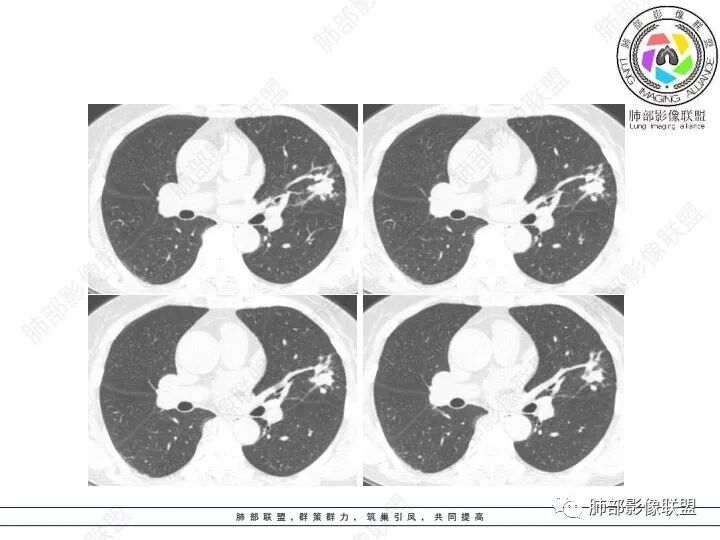

1、临床特点:61岁女性,体检发现肺结节。

2、影像特点:左肺上叶不规则病灶,冠状位、矢状位、斜状位重建显示病 灶整体沿着支气管方向呈斑片状,多结节堆积感明显,病灶大部分边缘显示平直,局部边缘稍膨隆,边界显示比较清楚,近端支气管壁显示增厚,周围可见长索条影及多发结节影,未显示典型“树芽征”。邻近叶间裂未受牵拉凹陷。纵隔窗显示病灶中央可见点状高密度钙化影。

3、病例小结:老年女性体检发现肺部结节,缺乏临床表现,需要警惕恶性。结合影像特点,左肺上叶病灶整体缺乏膨隆感,边缘大多平直,周围多发卫星灶(可见多发长索条影、并非肺CA的细短毛刺),病灶收缩力很弱(邻近叶间裂未见明显凹陷),观察1mm重建图亦可以发现病灶周围没有边界清楚的GGO,病灶内可见钙化点,肺门纵隔未见肿大淋巴结。综合以上,此病灶首先考虑炎性,结核可能性大,有条件可以增强扫描,有助于我们进一步判断。